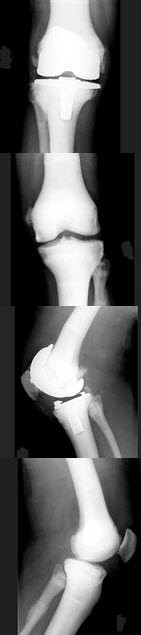

15、单项选择题

男,38岁,右肘关节外伤,结合图像,最可能诊断是()

男,15岁,右髋部疼痛、红肿,有压痛,皮温增高,结合图像,最可能的诊断是()

A.骨肉瘤

B.急性骨髓炎

C.尤文肉瘤

D.转移性神经母细胞瘤